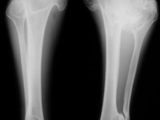

Multiple exostoses-legs

Multiple exostoses-legs